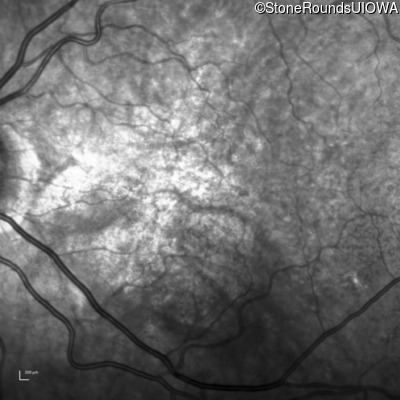

Age at visit: 58 years